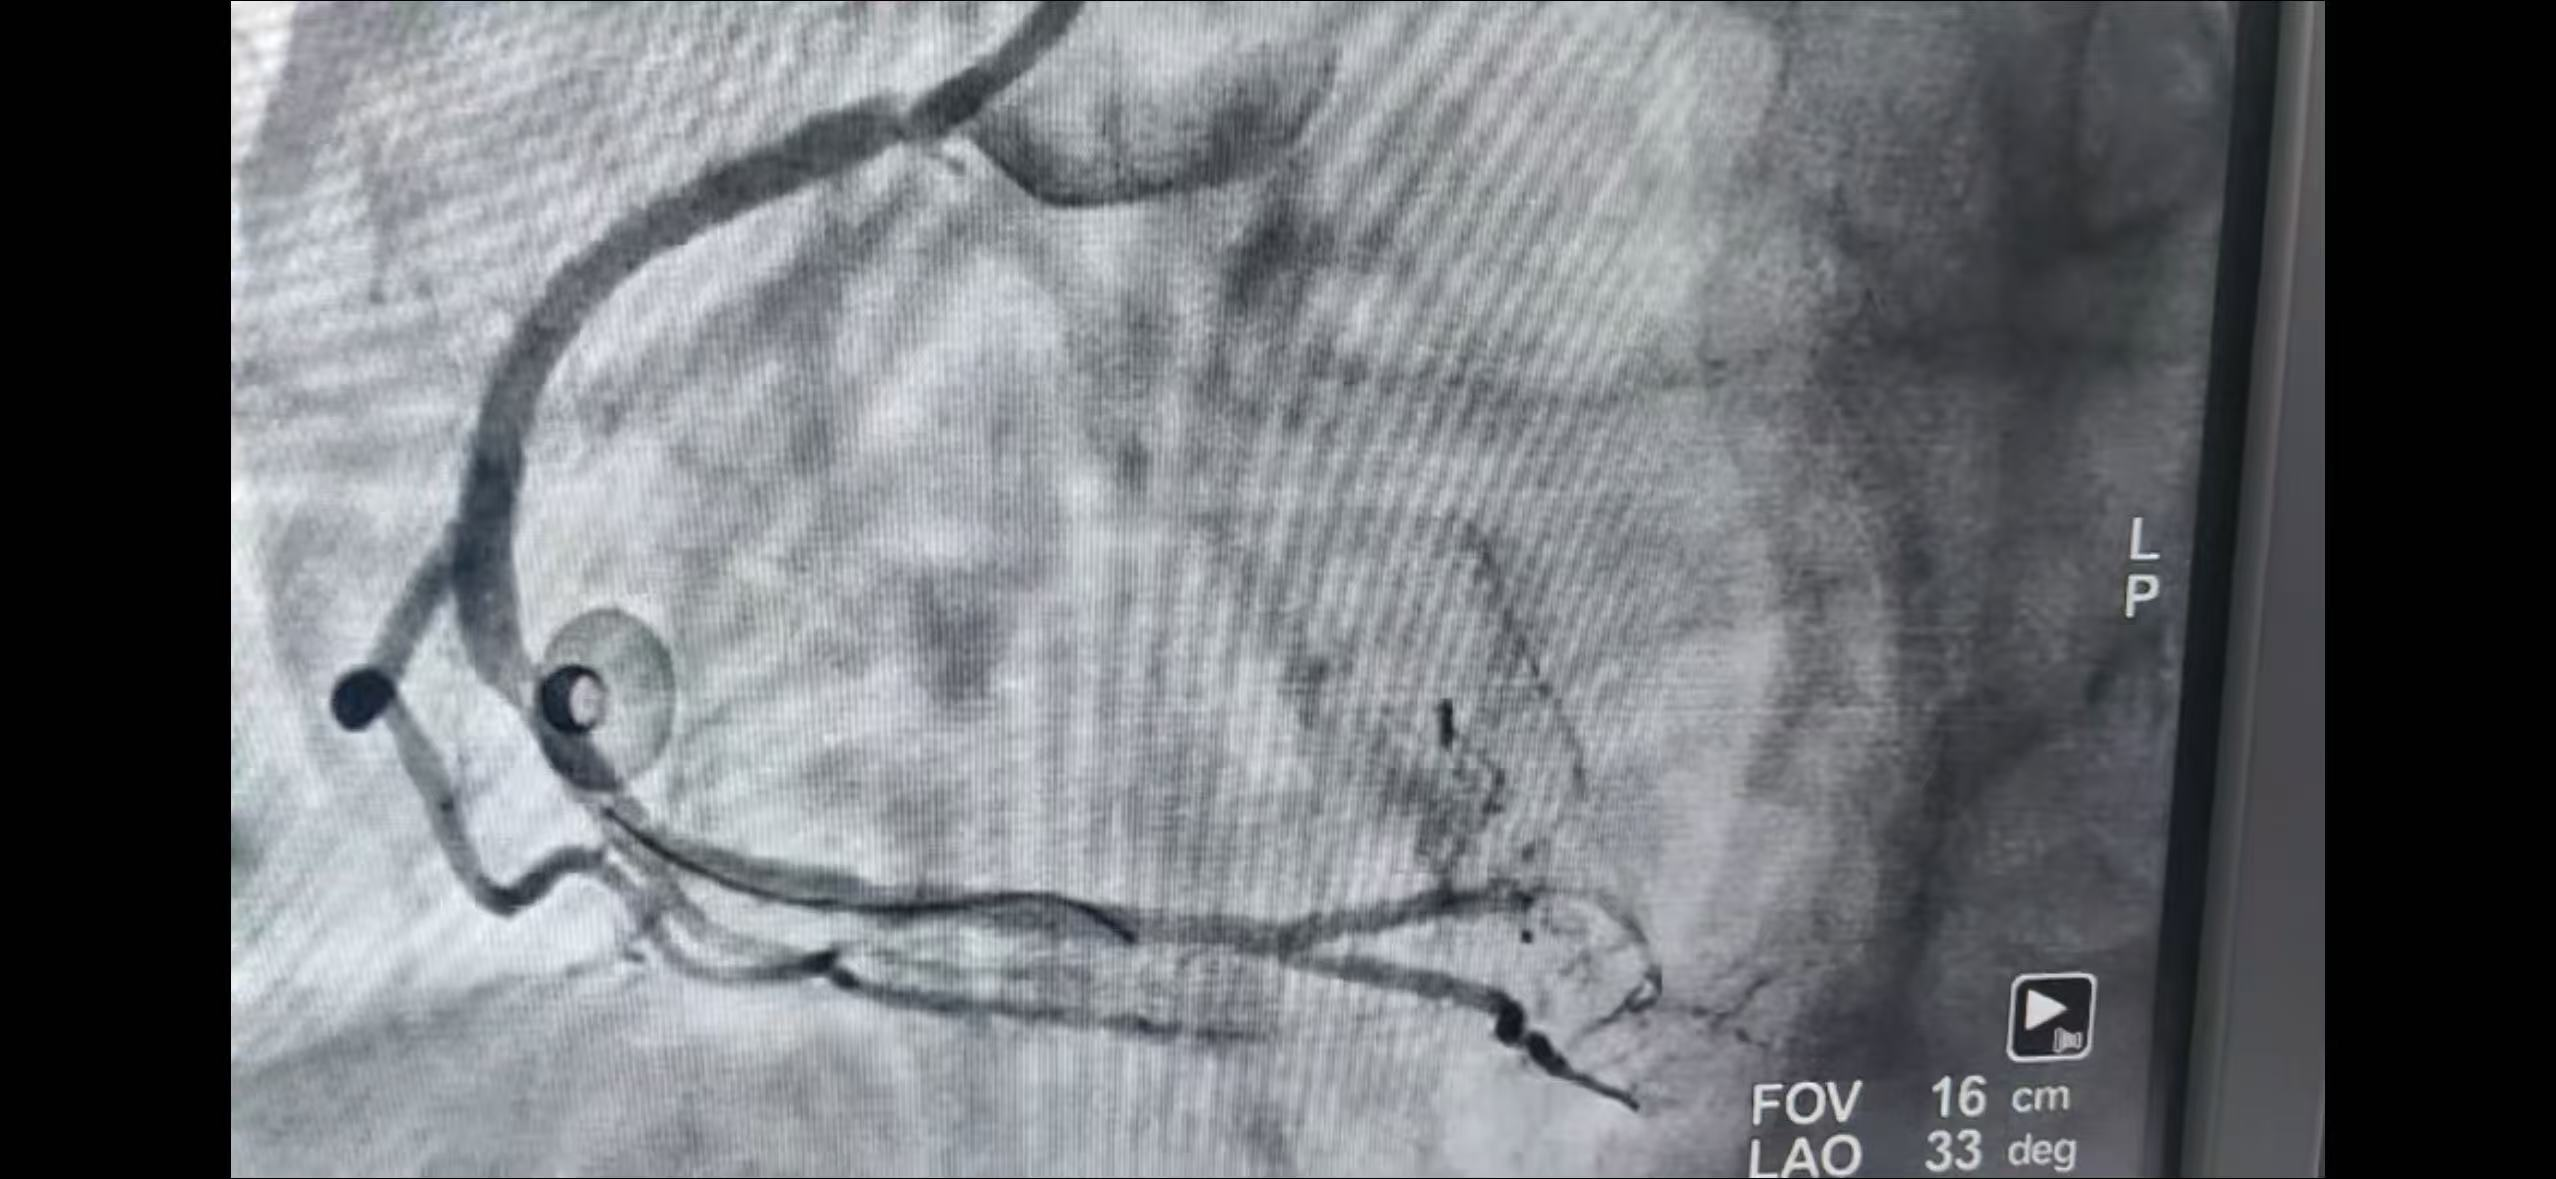

冠脉造影显示,患者冠脉三支血管严重病变,右冠近中段狭窄达95%,回旋支远段闭塞。手术团队当机立断,先行处理“罪犯血管”,成功实施RCA-PCI术。术后患者病情稳定,安返病房,拟择期行LAD-PCI、LCX-PCI术。经系统治疗与精心护理,患者恢复良好,于10月6日顺利出院。